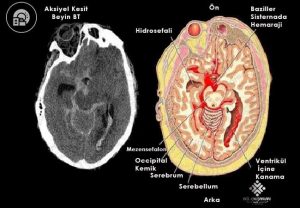

46 yaşında erkek hasta şiddetli baş ağrısı ve bilinç değişikliği nedeniyle acil servise başvuruyor. Acil servis hekimi hastayı değerlendirdiğinde: baş ağrısının ani başladığını, çok şiddetli olduğunu ve sonrasında hastada bilinç değişikli geliştiğini öğreniyor. Hastanın genel durumu kötü, oryente koopere değil, GKS 7, kan basıncı 240/100 mmHg, kalp hızı 88 atım/dk, oda havasında oksijen satürasyonu % 96 ve ateşi 36,5'C olarak saptanıyor. Fizik muayenede nöromotor net değerlendirilemiyor diğer sistemler doğal olarak değerlendiriyor. Acil hekimi hemen hastayı entübe ediyor, hastanda kan testi istiyor ve sonrasına aşağıda görüldüğü gibi kontrastsız beyin bt çektiriyor. Bu hasta için acil serviste en uygun tedavi yaklaşımı ne olmalıdır?

Subaraknoid kanama (SAK), kanın beyin omurilik sıvısının (BOS) bulunduğu pial ve araknoid membranlar arasındaki subaraknoid boşluğa (ekstravazasyon) kanın geçmesi durumudur. Travmatik veya spontan oluşabilir. En yaygın olanı kafa travması sonucunda travmatik meydana gelir. Travmatik olmayan subaraknoid kanamalar arteryel nadiren de venöz nedenlere bağlı olarak meydana gelir ve sıklıkla anevrizma rüptürü (% 85) sonucu ortaya çıkar. Orta ve ileri yaş grubunda önemli bir morbidite ve mortalite nedenidir. Anevrizmal SAK hastalarının klasik başvurusu tipik olarak “hayatımın en şiddetli baş ağrısı” olarak tanımlanan ani başlayan şiddetli bir baş ağrısıdır. Bu tür baş ağrısı olan her hasta SAK için mutlak değerlendirilmelidir. Baş ağrısı genellikle izole bir bulgudur. Hastalar çoğunlukla baş ağrısını “yıldırım çarpması” (thunderclap) şeklinde ani başlayan maksimum şiddete hızlı ulaşan şiddetli bir baş ağrısını şeklinde ifade ederler.